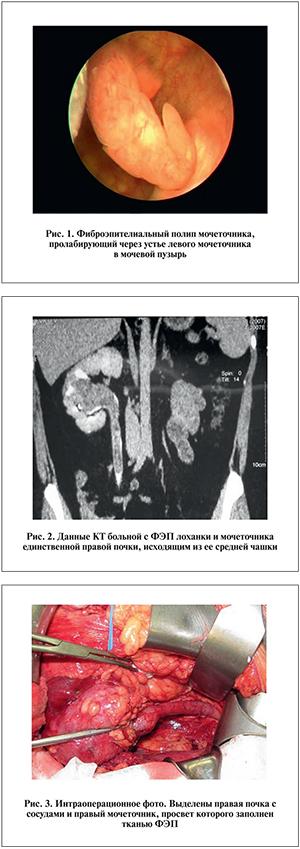

а) Терминология: 1. Синонимы: • Полип мочеточника с фиброэпителиальной структурой 2. Определение: • Благоприятное образование из мезодермальной ткани с гиперплазированным фиброзным основанием и нормальным уротелием

1. Общая характеристика: • Основной диагностический признак: о Продолговатое образование с мягкотканной консистенцией внутри полости с гладкой поверхностью • Местонахождение: о Чаще всего слева о Чаще всего в верхней трети • Размер: о Разный; может достигать 12 см • Морфология: о Продолговатый дефект наполнения внутри полости с гладкой поверхностью

3. При наличии полипов мочеточника на компьютерной томографии (КТ) выявляются следующие особенности: • Внутри просвета мочеточника виден продолговатый образование, имеющее мягкотканную плотность и гладкую поверхность • Полипы аккумулируют контрастное вещество • Полипы имеют тонкую и худую форму, напоминающую штопор или червь • На КТ или ультразвуковом исследовании может наблюдаться выпячивание полипа через устье мочеточника в мочевой пузырь • Возможно наличие гидроуретера или гидронефроза • Изображения в отсроченной фазе (на картинах КТ-урографии) помогают более точно определить форму и контур полипов • КТ исследование помогает исключить другие причины обструкции, такие как камень или другие нарушения.

4. УЗИ при наличии полипов в мочеточнике: • При УЗИ видно червеобразное движение полипа мочеточника, который выступает в мочевой пузырь • Подвижность является важным критерием для исключения уротелиального образования (уротелиальные образования не двигаются и закреплены на месте) • Допплерография помогает определить кровоснабжение опухоли (этот критерий позволяет отличить полип от сгустка крови)

5. Рекомендации по визуализации: • Лучший метод визуализации: о КТ-урография является предпочтительным методом для исследования обструктивных образований

(Слева) В переднебоковой проекции показана ретроградная пиелография: внутри просвета дистального отдела левого мочеточника виден явный дефект наполнения с четкими краями. При патоморфологическом исследовании обнаружен фиброэпителиальный полип. Наличие хирургических клипс в тазу слева указывает на предшествующую гистерэктомию. (Справа) В переднебоковой проекции показана ретроградная пиелография: внутри просвета дистального отдела мочеточника слева виден продолговатый дефект наполнения с четкими краями. При цистоскопии обнаружено полипоидное образование с длинной шейкой, которое периодически выпячивало через устье мочеточника.

(Слева) При проведении компьютерной томографии на уровне входа в малый таз, в аксиальном срезе, было обнаружено умеренное расширение мочеточника слева. (Справа) При проведении компьютерной томографии малого таза с контрастированием у этого же пациента была выявлена контрастируемая мягкая ткань в дистальной части мочеточника слева. При последующей ретроградной пиелографии и цистоскопии было обнаружено внутрипросветное полипоидное образование. Для удаления полипа пациенту была выполнена трансуретральная процедура. При патоморфологическом исследовании был обнаружен фиброэпителиальный полип.

2. Макроскопические и хирургические особенности: • Полипоидное образование имеет розовато-бронзовый цвет и гладкую поверхность

3. Микроскопия: • В строме присутствует рыхлая сосудистая фиброзная ткань, покрытая нормальным переходным эпителием